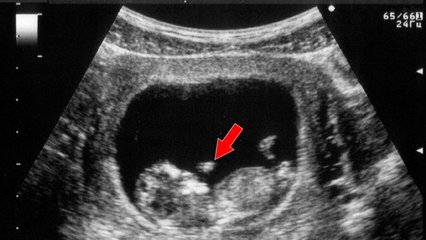

double you 58 jours de gestation